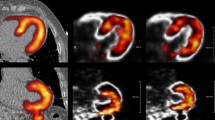

The 600 images were shown as pairs (NMC and DDMC) to two observers (IA, MM) in the format of short, horizontal and vertical long axis slices obtained from Cedars Sinai QPET (Cedars Sinai, Los Angeles, CA, United States). All images were blinded, to the extent that the observers did not know which image was NMC and which was DDMC, and randomized. The two observers were asked to define a Visual Difference Score (VDS) of 0, 1 or 2, which represented the following: 0: no difference perceivable between the images; 1: a subtle difference perceivable between the images and 2: a clear difference between the images. Areas that the observers were asked to take note of were homogeneity and intensity of uptake in the myocardium, separation between the myocardium and surrounding extra-cardiac activity and clarity of the ventricular cavity. Figure 1 gives examples of image pairs rated a VDS of 1 and 2. Following assessment by the two observers, any differences in VDS classification across image pairs were discussed jointly and a consensus score was assigned to produce a single table of values.

Demonstration of characteristics that were used to attribute the corresponding visual difference scores (VDS) for non-motion-corrected (NMC) compared with the motion-corrected images (DDMC). Image pair (A) shows subtle improvement to the separation of the inferior wall from extra-cardiac activity; image pair (B) shows subtle improvement to the inferior wall intensity; image pairs (C) and (D) show clear improvement to the overall definition and intensity of the myocardium, while image pair (D) also shows clear improvement of the separation of the inferior wall from extra-cardiac activity